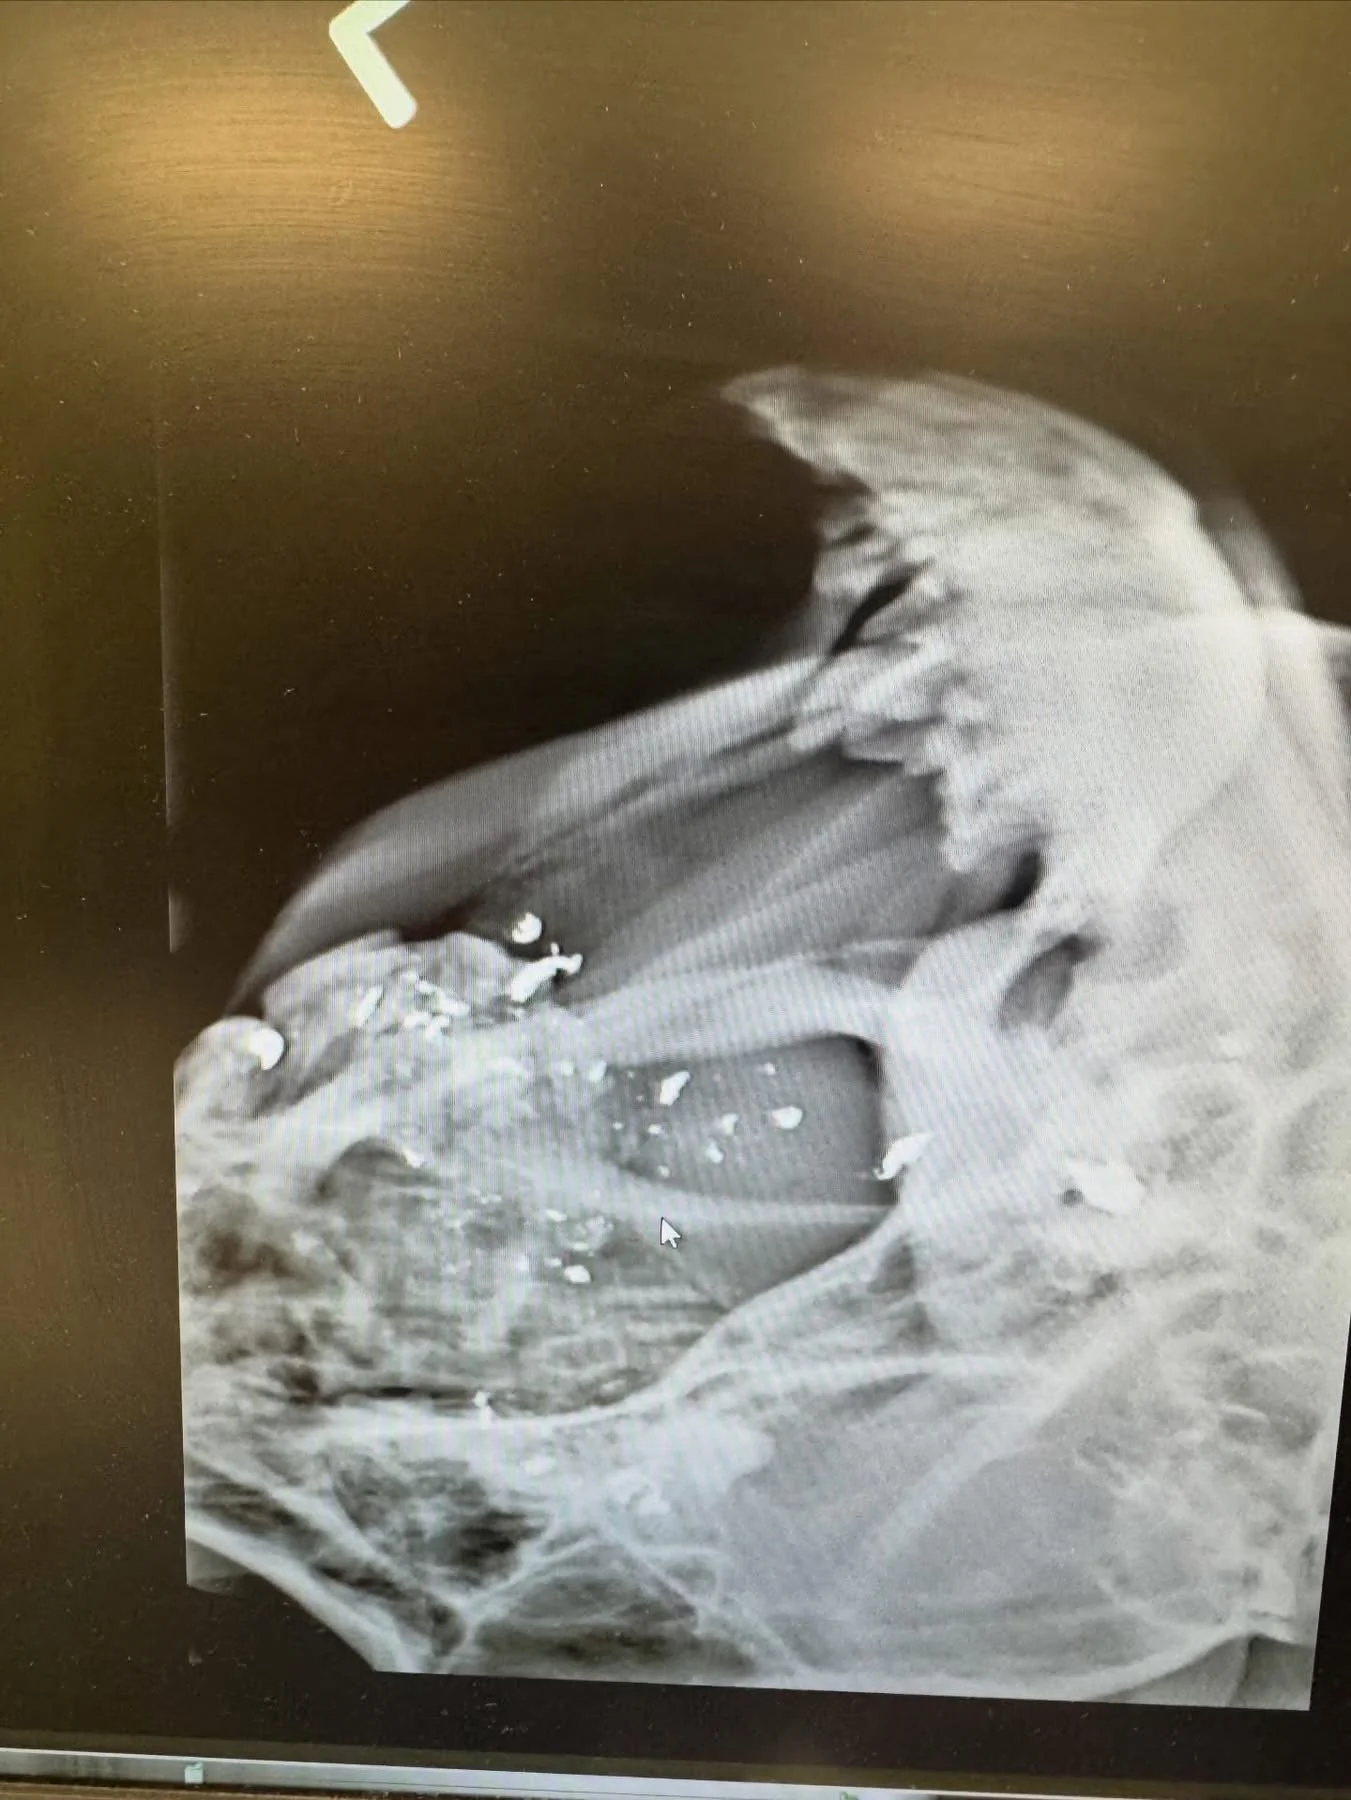

We finally got her safely into my car and dropped her off at the vet. The bullet had gone right through her cheek, tongue, and into her brain. Unfortunately, there’s not much we can do except strong pain medication, antibiotics, and hope 🙏 for a positive outcome.